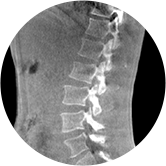

• 腰椎

三维脊柱应用

精准诊断

手术方案规划

术后随访

传统方法都是在二维平面,依靠棘突或椎弓根相对于椎体的偏移来评估脊柱侧凸。WR-3D可以更精准评估脊柱侧凸,制定手术方案,可以更直观地显示和量化椎体的平移和轴向旋转,术后评估更准确客观。